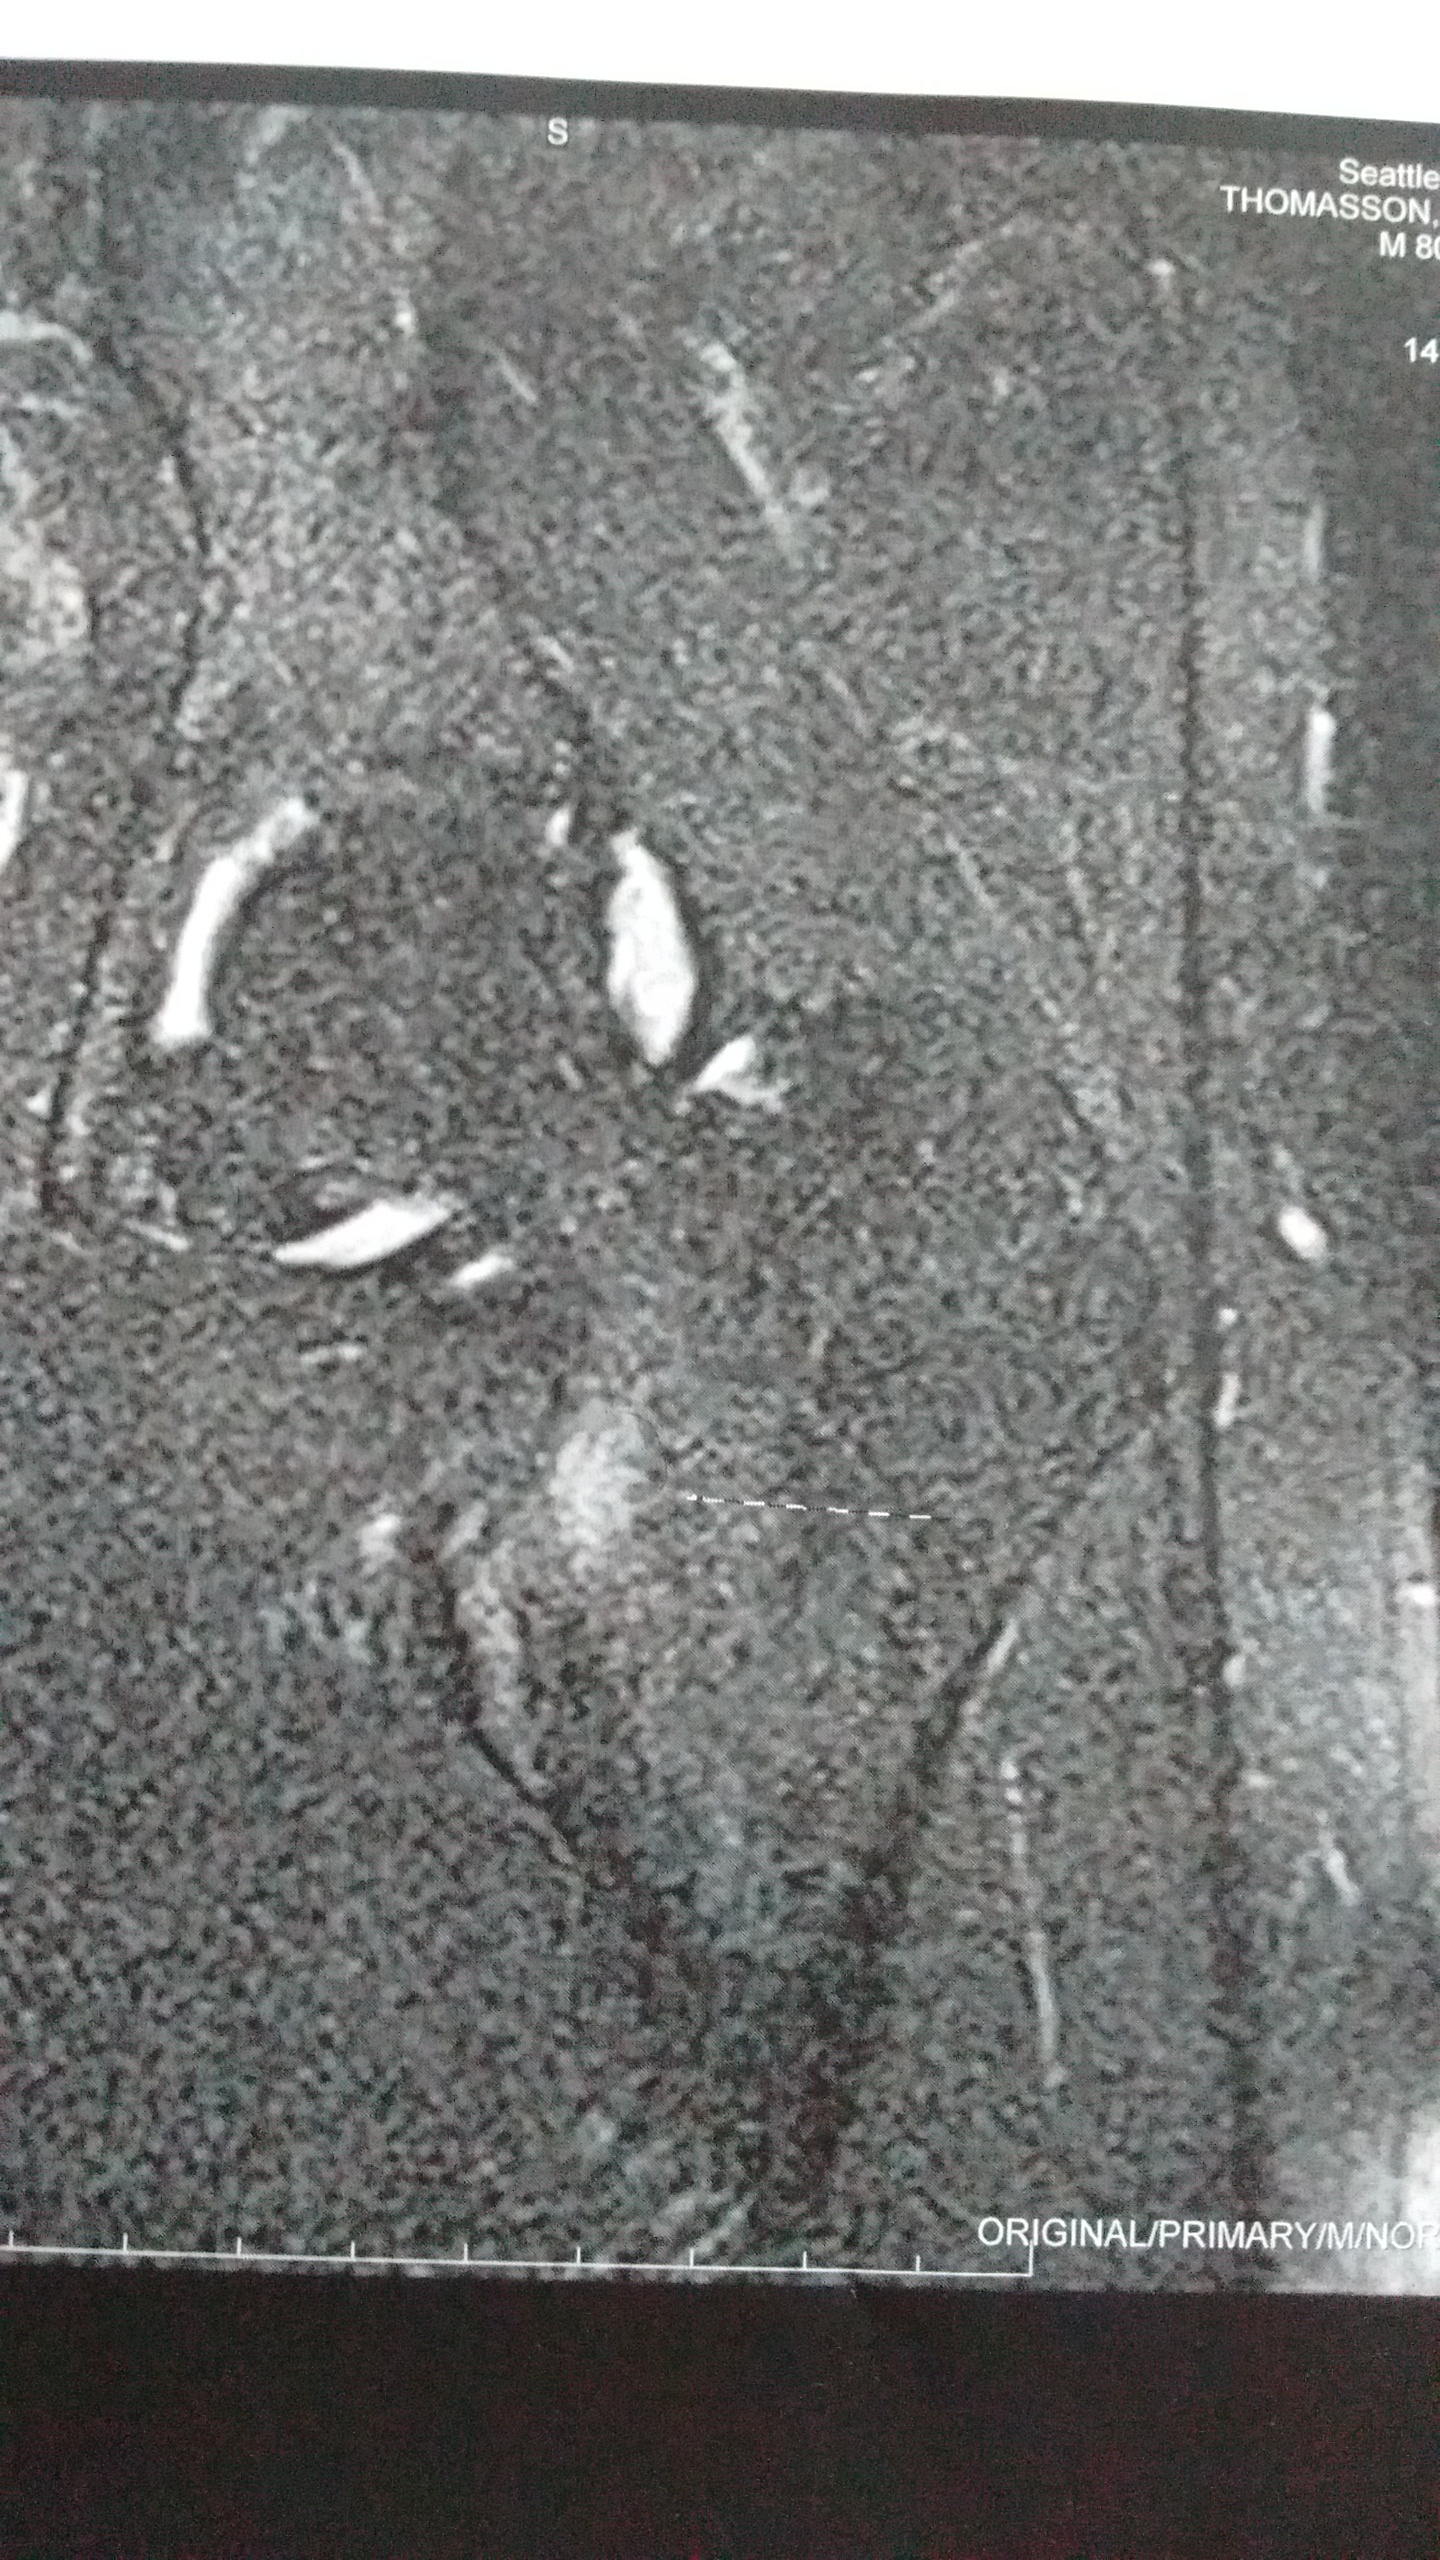

Today I returned to the doctor for my stress fracture treatment plan, and I left the office on crutches. However, I actually found out some good news. My fracture hadn’t actually progressed to an actual visible fracture yet. That glowing smudge on the hip bone is the beginning stages of a stress fracture: inflammation and micro-fractures. As you can see, it’s on the bottom of the femoral neck. This is called a compression stress fracture. If it had been on the top (tension), then there would have been a great likelihood of having surgery. So, I’m very thankful it’s on the bottom.